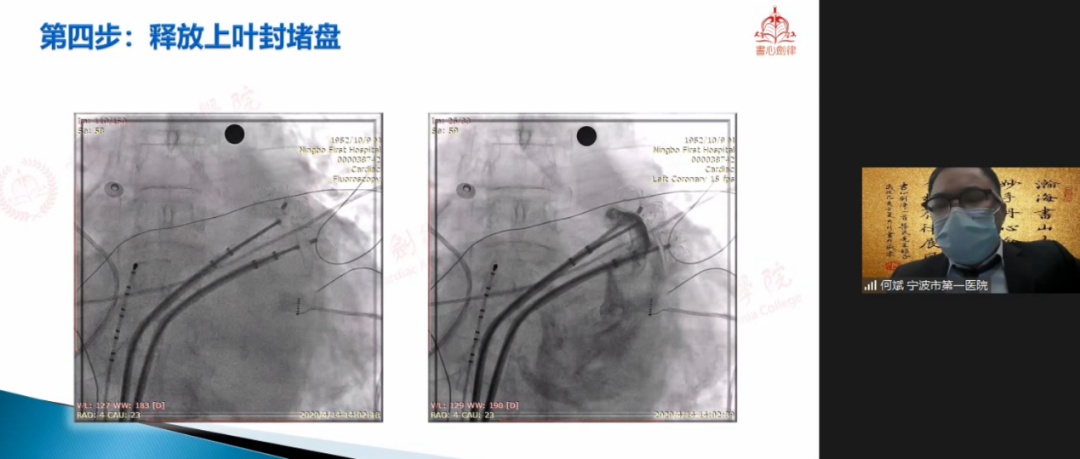

何斌教授

孝感市第一医院何斌教授在会议中与专家们共享LAmbre?双伞封堵大心耳经验。该病例为81岁男性,被诊断为持续性心房抖动,CHA2DS2-VASc评分6分、HAS-BLED评分4分,既往有左心耳血栓、卒中病史?鼓街6月后,TEE下未见心耳血栓。术中DSA造影提醒患者为双早分叶心耳,上叶梳状肌蓬勃,下叶较为光滑,心耳口部直径45mm。已有临床事俘批注,LAmbre?行双伞封堵拥有可行性,结合患者情况、眷属意愿及心耳状态等多种成分,何斌教授最终拟定为患者行双伞封堵战术。何斌教授首先行两次房距离穿刺并再次造影确认心耳状态及大幼,丈量得上壹定区21.6mm,下壹定区19.4mm,随后选用LAmbre?2228封堵器先行封堵下叶,牵拉测试不变后,选择LAmbre?2430封堵器封堵心耳上叶。最终,双伞牵拉测试不变,TEE多角度评估双伞状态优良,缜密贴合,无显著残存分流,一年后随访了局显示,封堵成效优良,无卒中事务产生。